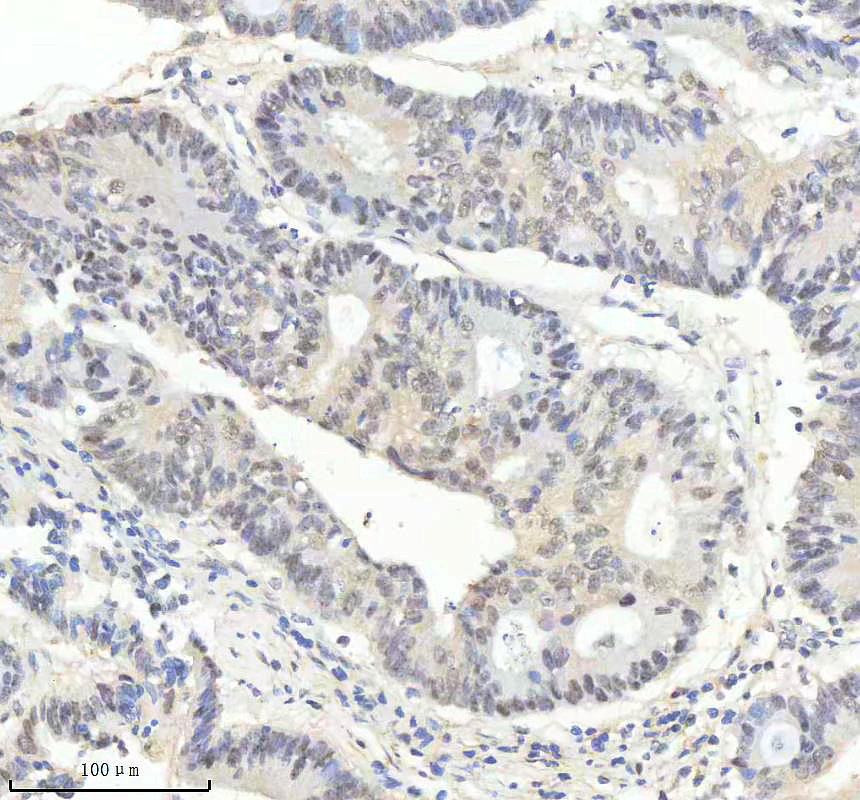

IHC analysis of P-PRKCA using anti-P-PRKCA antibody (BM4896).

P-PRKCA was detected in a paraffin-embedded section of human pancreas cancer tissue. The tissue section was incubated with rabbit anti-P-PRKCA Antibody (BM4896) at a dilution of 1:200 and developed using HRP Conjugated Rabbit IgG Super Vision Assay Kit (Catalog # SV0002) with DAB (Catalog # AR1027) as the chromogen.